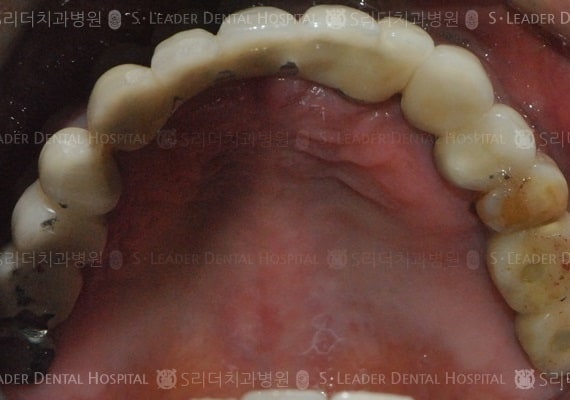

전체임플란트, 14년 2개월 경과